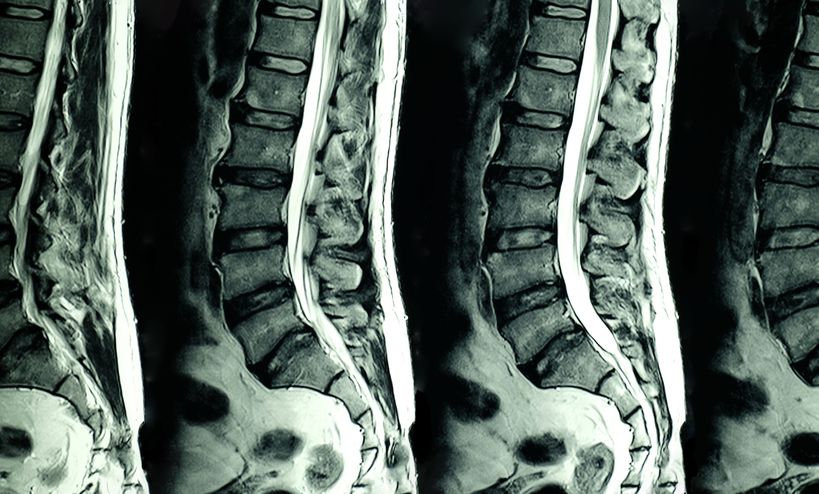

STA363 can offer a Potential Turning Point: Innovation through disease modification in a Common Condition, pain caused by Lumbar Disc Herniation

While many recent innovations have targeted small patient populations, new therapies in development hold promise for addressing widespread conditions with significant economic and clinical impacts. One important example is STA363, a novel agent in early clinical trials for lumbar disc herniation (LDH), a common cause of back pain.

If approved, STA363 could revolutionize the treatment paradigm by offering a disease-modifying effect that relieves pain, reduces potential for opioid addiction and prevents surgery. Unlike the current standard of care-which is expensive, costs being noted as up to $150,000, and involves multiple physician visits, pain management medications, physical therapy, acupuncture, chiropractic care, and often surgery-this single-injection treatment could provide:

Stayble is a clinical pharmaceutical company developing the injection treatment STA363 for lumbar disc herniation (LDH). Stayble's vision is to offer patients a simple and effective treatment that targets the underlying cause of the patient's chronic pain and provides lasting pain relief and increased physical function. The treatment is aimed at patients who are not helped by physical therapy and painkillers and is a single injection that is expected to last a lifetime and requires minimal rehabilitation. After convincing data from previous pre-clinical and clinical studies (phase 1b and 2b) in degenerative disc disease, which show a volume reduction of the discs, the Company has successfully completed a phase 1b study for the treatment of herniated discs.